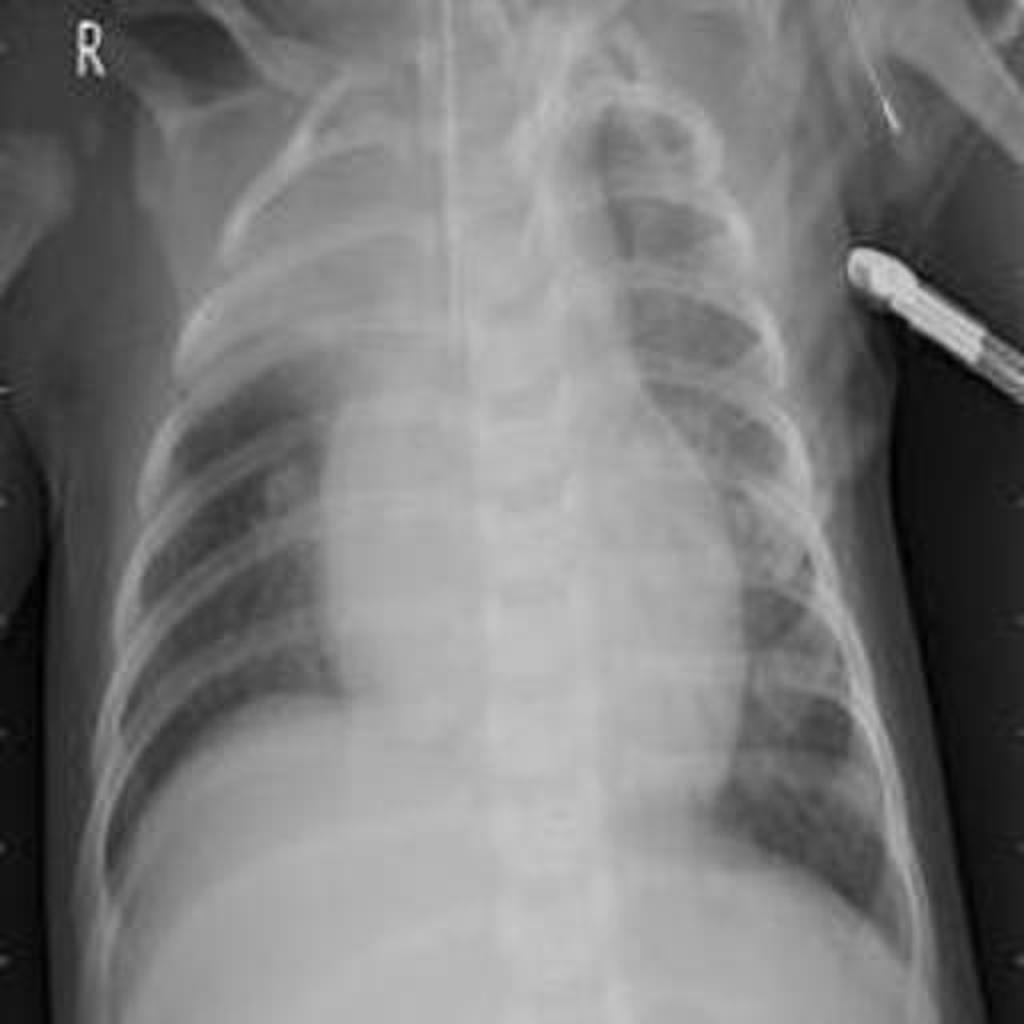

In this project ,we aim to propose a fully-automated method to detect/screen COVID-19 from the patient’s chest X-ray scanned images with out needing a clinical technician.

I've teamed up with AI enthusiasts and got inspired from the several news articles to create a end to end web application using Deep learning.We have collected datasets from Mendeley and Qatar University which were posted on kaggle website.We augumented the images and trained the model to detect the hidden patterns in the images and using "Transfer Learning" approach we have used the model to deploy it on cloud platform and hooked it via flask server.

The main challenge was the dataset of X-ray images from medical institutions. Unitl now the Covid19 dataset is not shared to public by most of the countries which could have paved the way for more developers or scientists to find out a better way to deal with this pandemic